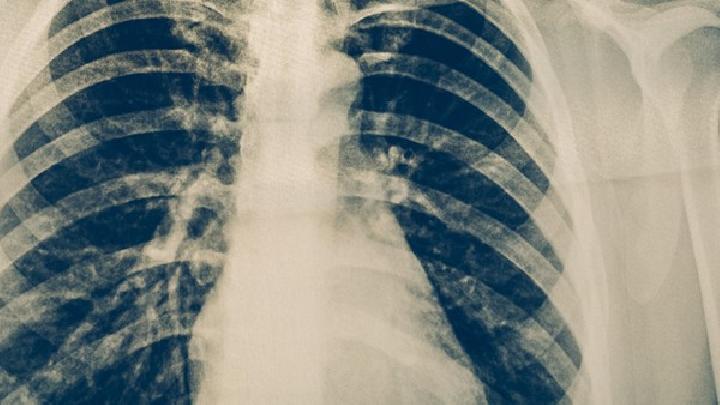

肺癌是最常见的肺原发性恶性肿瘤。肺癌目前是全世界癌症死因的第一名。肺癌多发于男性,可是近年来,女性肺癌的发生率明显上升,那么这是为什么呢?据调查:女性除了有“二手烟”的危害外,厨房油烟也是肺癌的一项重要致病因素。